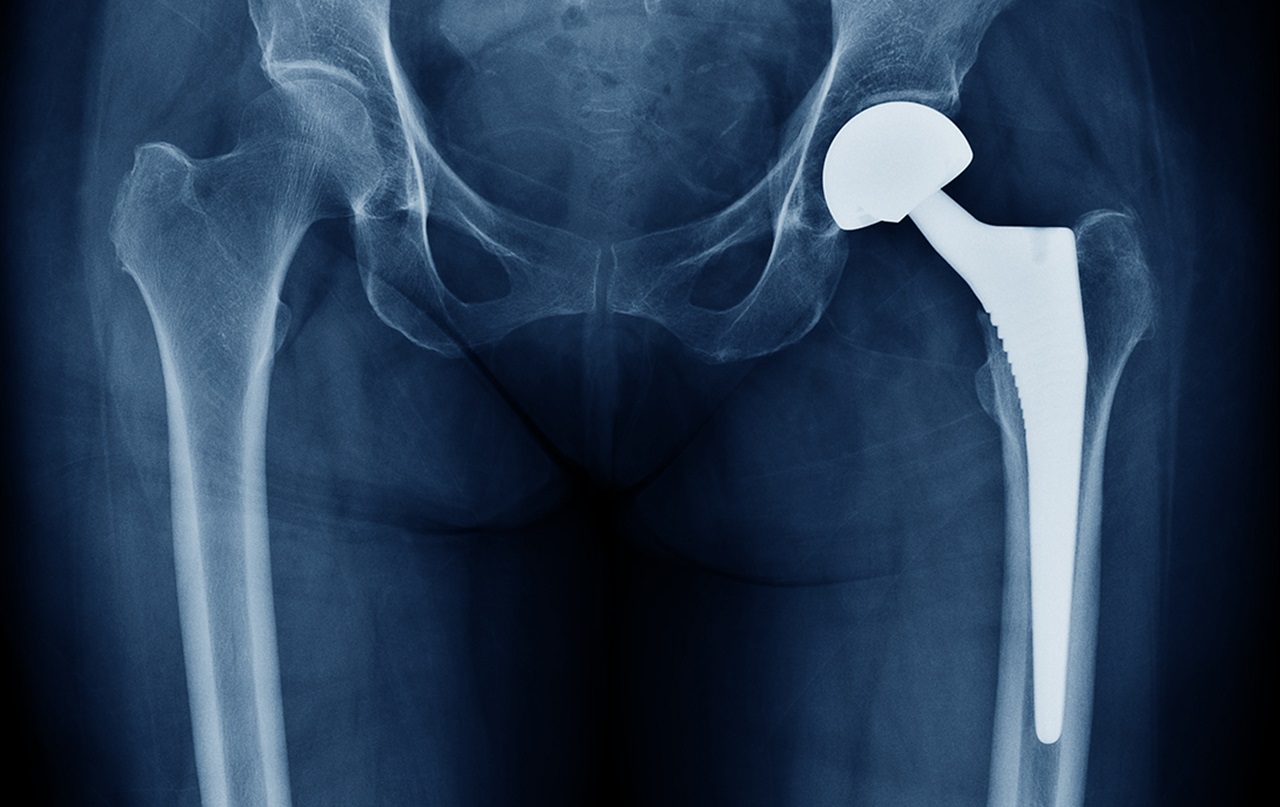

If you have had a joint replacement and taken antibiotics before dental work in the past, you may not need to make a trip to the pharmacy before your next procedure. The American Dental Association has found it is no longer necessary for most dental patients with orthopedic implants to have antibiotic prophylaxis to prevent infection.

Prior to 2012, premedication prior to dental procedures was common for joint replacement patients, even though there was little evidence to support the practice and experts recommended against its practice for most dental patients. In 2012, the American Dental Association and American Association of Orthopedic Surgeons published updated guidelines, stating that dentists “might consider discontinuing the practice of routinely prescribing prophylactic antibiotics”. In January 2015, the ADA’s Council on Scientific Affairs issued another guideline, which continued to discourage prophylactic antibiotic use for most patients with prosthetic joint implants. Guidelines are re-evaluated every few years to make sure that they are based on the best scientific evidence.

Based on careful review of the scientific literature, the ADA found that dental procedures are not associated with prosthetic joint implant infections, and that antibiotics given before dental procedures do not prevent such infections.